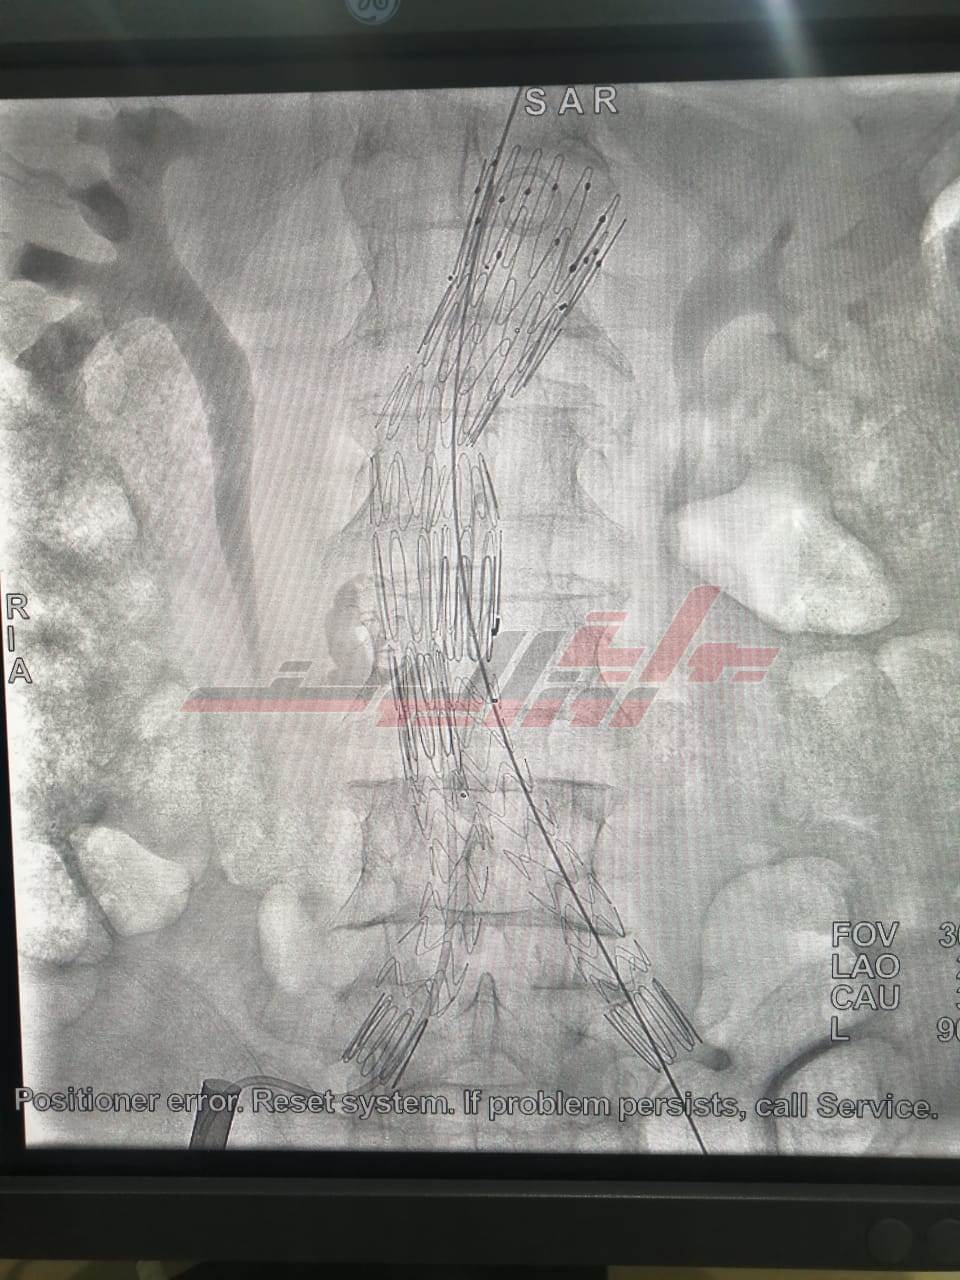

أعلن الدكتور مصطفى القاضي، عميد كلية الطب البشري، ورئيس مجلس إدارة مستشفيات بنها الجامعية، أنه لأول مرة يتم تركيب دعامة مغطاة لتمدد بالشريان الاورطي البطني لمريض يبلغ من العمر 80 عاما يصعب فيه التدخل الجراحي.

وأشار القاضى إلى أنه تم الإستعانة بالدكتور شريف عمر الكرداوي لإجراء العملية بمستشفيات بنها الجامعية، وذلك باستخدام التقنيات الحديثه داخل وحدة جراحة الأوعية الدموية والقسطرة التداخلية، وقد تمت العملية بنجاح والمريض في حالة جيدة داخل مستشفى بنها الجامعي لاستكمال البرنامج العلاجي.